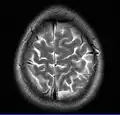

MRI image of the surface of the brain.